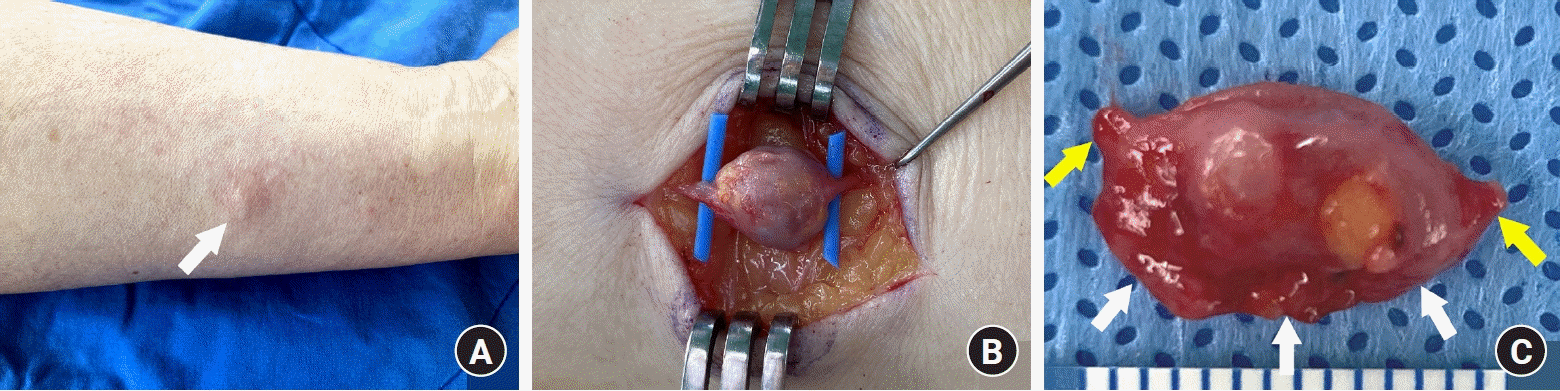

A 76-year-old man presented to our clinic with a painful, long-standing subcutaneous lump on his left forearm. The lesion, first noticed over two decades ago as an asymptomatic, tiny bump, had gradually enlarged over time. The patient had experienced increasingly frequent paroxysmal pain for the past 3 years, and the lump had become sensitive to touch. During the evaluation, the patient exhibited significant protectiveness over the affected area and flinched upon contact. Upon physical examination, a 1.2-cm movable, tender subcutaneous nodule was identified on the ulnovolar aspect of the patient’s left forearm, with brownish discoloration of its overlying skin (Fig. 1A). Preoperative magnetic resonance imaging (MRI) revealed a 1.2 × 1.1 × 0.9-cm subcutaneous mass in the anterior forearm with low T1-weighted signal intensity that avidly enhanced with contrast and high-intensity signal on T2-weighted imaging (Fig. 2).

Under general anesthesia, the lesion was explored carefully, revealing a bluish-red, round-shaped tumor with tubular structures extending from both ends (Fig. 1B). Given the uncertainties of the tubular structures, we considered that intraoperative confirmation of the tumor’s origin was necessary for definitive treatment. Although typical nerve appearances, including fascicles, were not observed, the lesion was not resected immediately; instead, the intracapsular lesion was enucleated by longitudinally splitting the tumor capsule, which was then sent for frozen section pathology. A well-demarcated, brownish lesion was easily separated from the inner capsule wall, save for a small adherent segment. The frozen section pathology suggested the lesion to be a GT. The remaining tumor capsule was also excised and submitted for permanent section pathology. The surgical wound was closed primarily after inserting a small silastic drain.

Microscopic examination revealed an encapsulated tumor comprising solid sheets of blue cells, which consisted of round glomus cells with increased vascular spaces (Fig. 3A, 3B). The neoplastic cells were positive for smooth muscle actin immunostaining (Fig. 3C). Sectional views of the tubular structure attached to the tumor revealed the presence of a blood vessel (Fig. 4A, 4B). Notably, a compressed luminal space, positive for the vascular marker CD31, was identified on the tumor’s undersurface (Fig. 4C), indicating a potential connection between the blood vessel of the tumor’s undersurface and the tubular structures (Fig. 1C). These histopathological features suggested that the GT had exerted chronic pressure on the underlying blood vessels, resulting in firm adherence of the vessel to the tumor. Postoperative recovery was uneventful, and the paroxysmal pain resolved immediately following surgery. The patient reported excellent postoperative outcomes at the 3-month follow-up with no observed complications.

Fig. 1.

Clinical and operative features. (A) A 1.2-cm subcutaneous nodule on the ulnovolar aspect of the left forearm (arrow). (B) A bluish-red, round-shaped tumor with tubular structures extending from both ends. (C) A lateral aspect of the resected lesion showing a tubular structure (white arrows) attached to the tumor’s undersurface and connected to both stalks (yellow arrows).